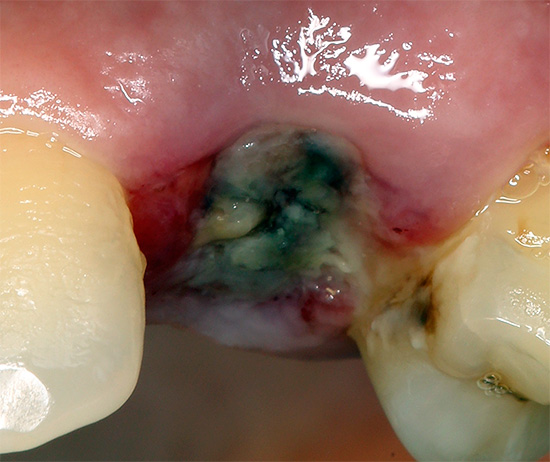

Se houver sinais associados ao desenvolvimento de complicações no orifício do dente extraído, na maioria das vezes é a alveolite (inflamação das paredes do orifício), que geralmente aparece nos próximos 2-3 dias após o procedimento. A alveolite se manifesta por sintomas característicos da supuração da ferida: dor, halitose, formação de placa cinza ao redor da cavidade dental, supuração da mesma, inflamação dos gânglios linfáticos, intoxicação do corpo com aumento da temperatura corporal.

Se a alveolite for diagnosticada, o dentista realiza anestesia de alta qualidade e realiza curetagem (purificação) do orifício a partir de um coágulo de sangue em decomposição e, às vezes, também a partir de restos não removidos anteriormente de partículas de um dente doente, granulomas, cistos, com a lavagem dos poços com soluções anti-sépticas. Se necessário, a ferida pode ser suturada. Depois disso, são prescritos medicamentos antibacterianos, na maioria das vezes para uso tópico na forma de lavagens ou pomadas.